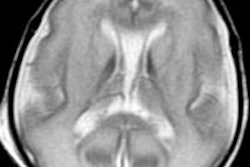

However, using 12-tesla MRI, Back and colleagues identified tiny brain lesions in preterm fetal sheep with characteristics previously unseen and unreported using a standard 3-tesla MRI.

The findings support the potential of using high-field MRI for early identification and improved diagnosis and prognosis of white-matter injury in preterm infants, Back said. The "preclinical animal model provides unique experimental access to questions directed at the cause of these lesions, as well as the optimal field strength and modality to resolve evolving lesions using MRI," he added.